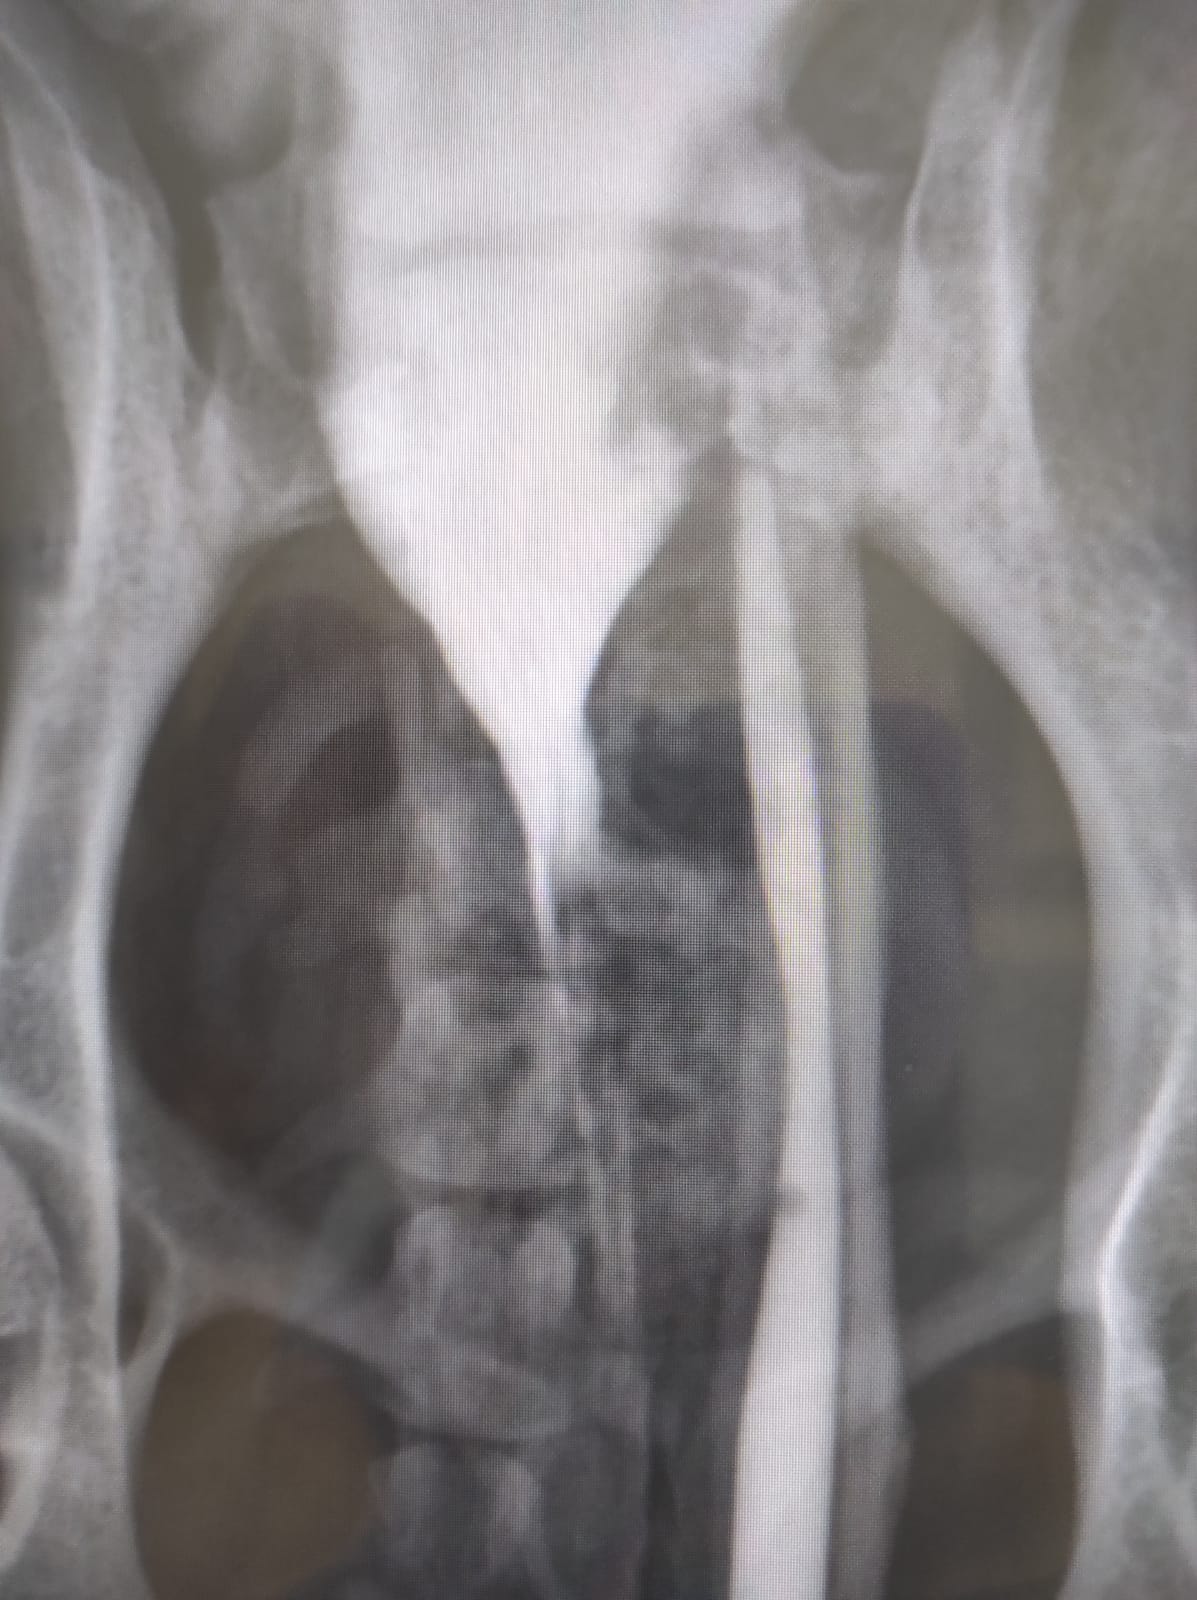

Dobrý den, prosím o radu, na veterině zjistili, že má muj pejsek dvě močove trubice. Diagnoza je "za os penis se uretra rozdvojuje na 2 samostatné uretry, samostatně ústící do moč. měchýře. Uretra duplex". Jaké je možné chirurgické řešení? Náš DR se taky musí s někým poradit, řekl, že je to rartiní. Zatím má náš pejsek zánět a zpusobuje mu to potíže pri močení, mal antibiotika, no zatim to úplně nepomohlo. Ďekuji Romana